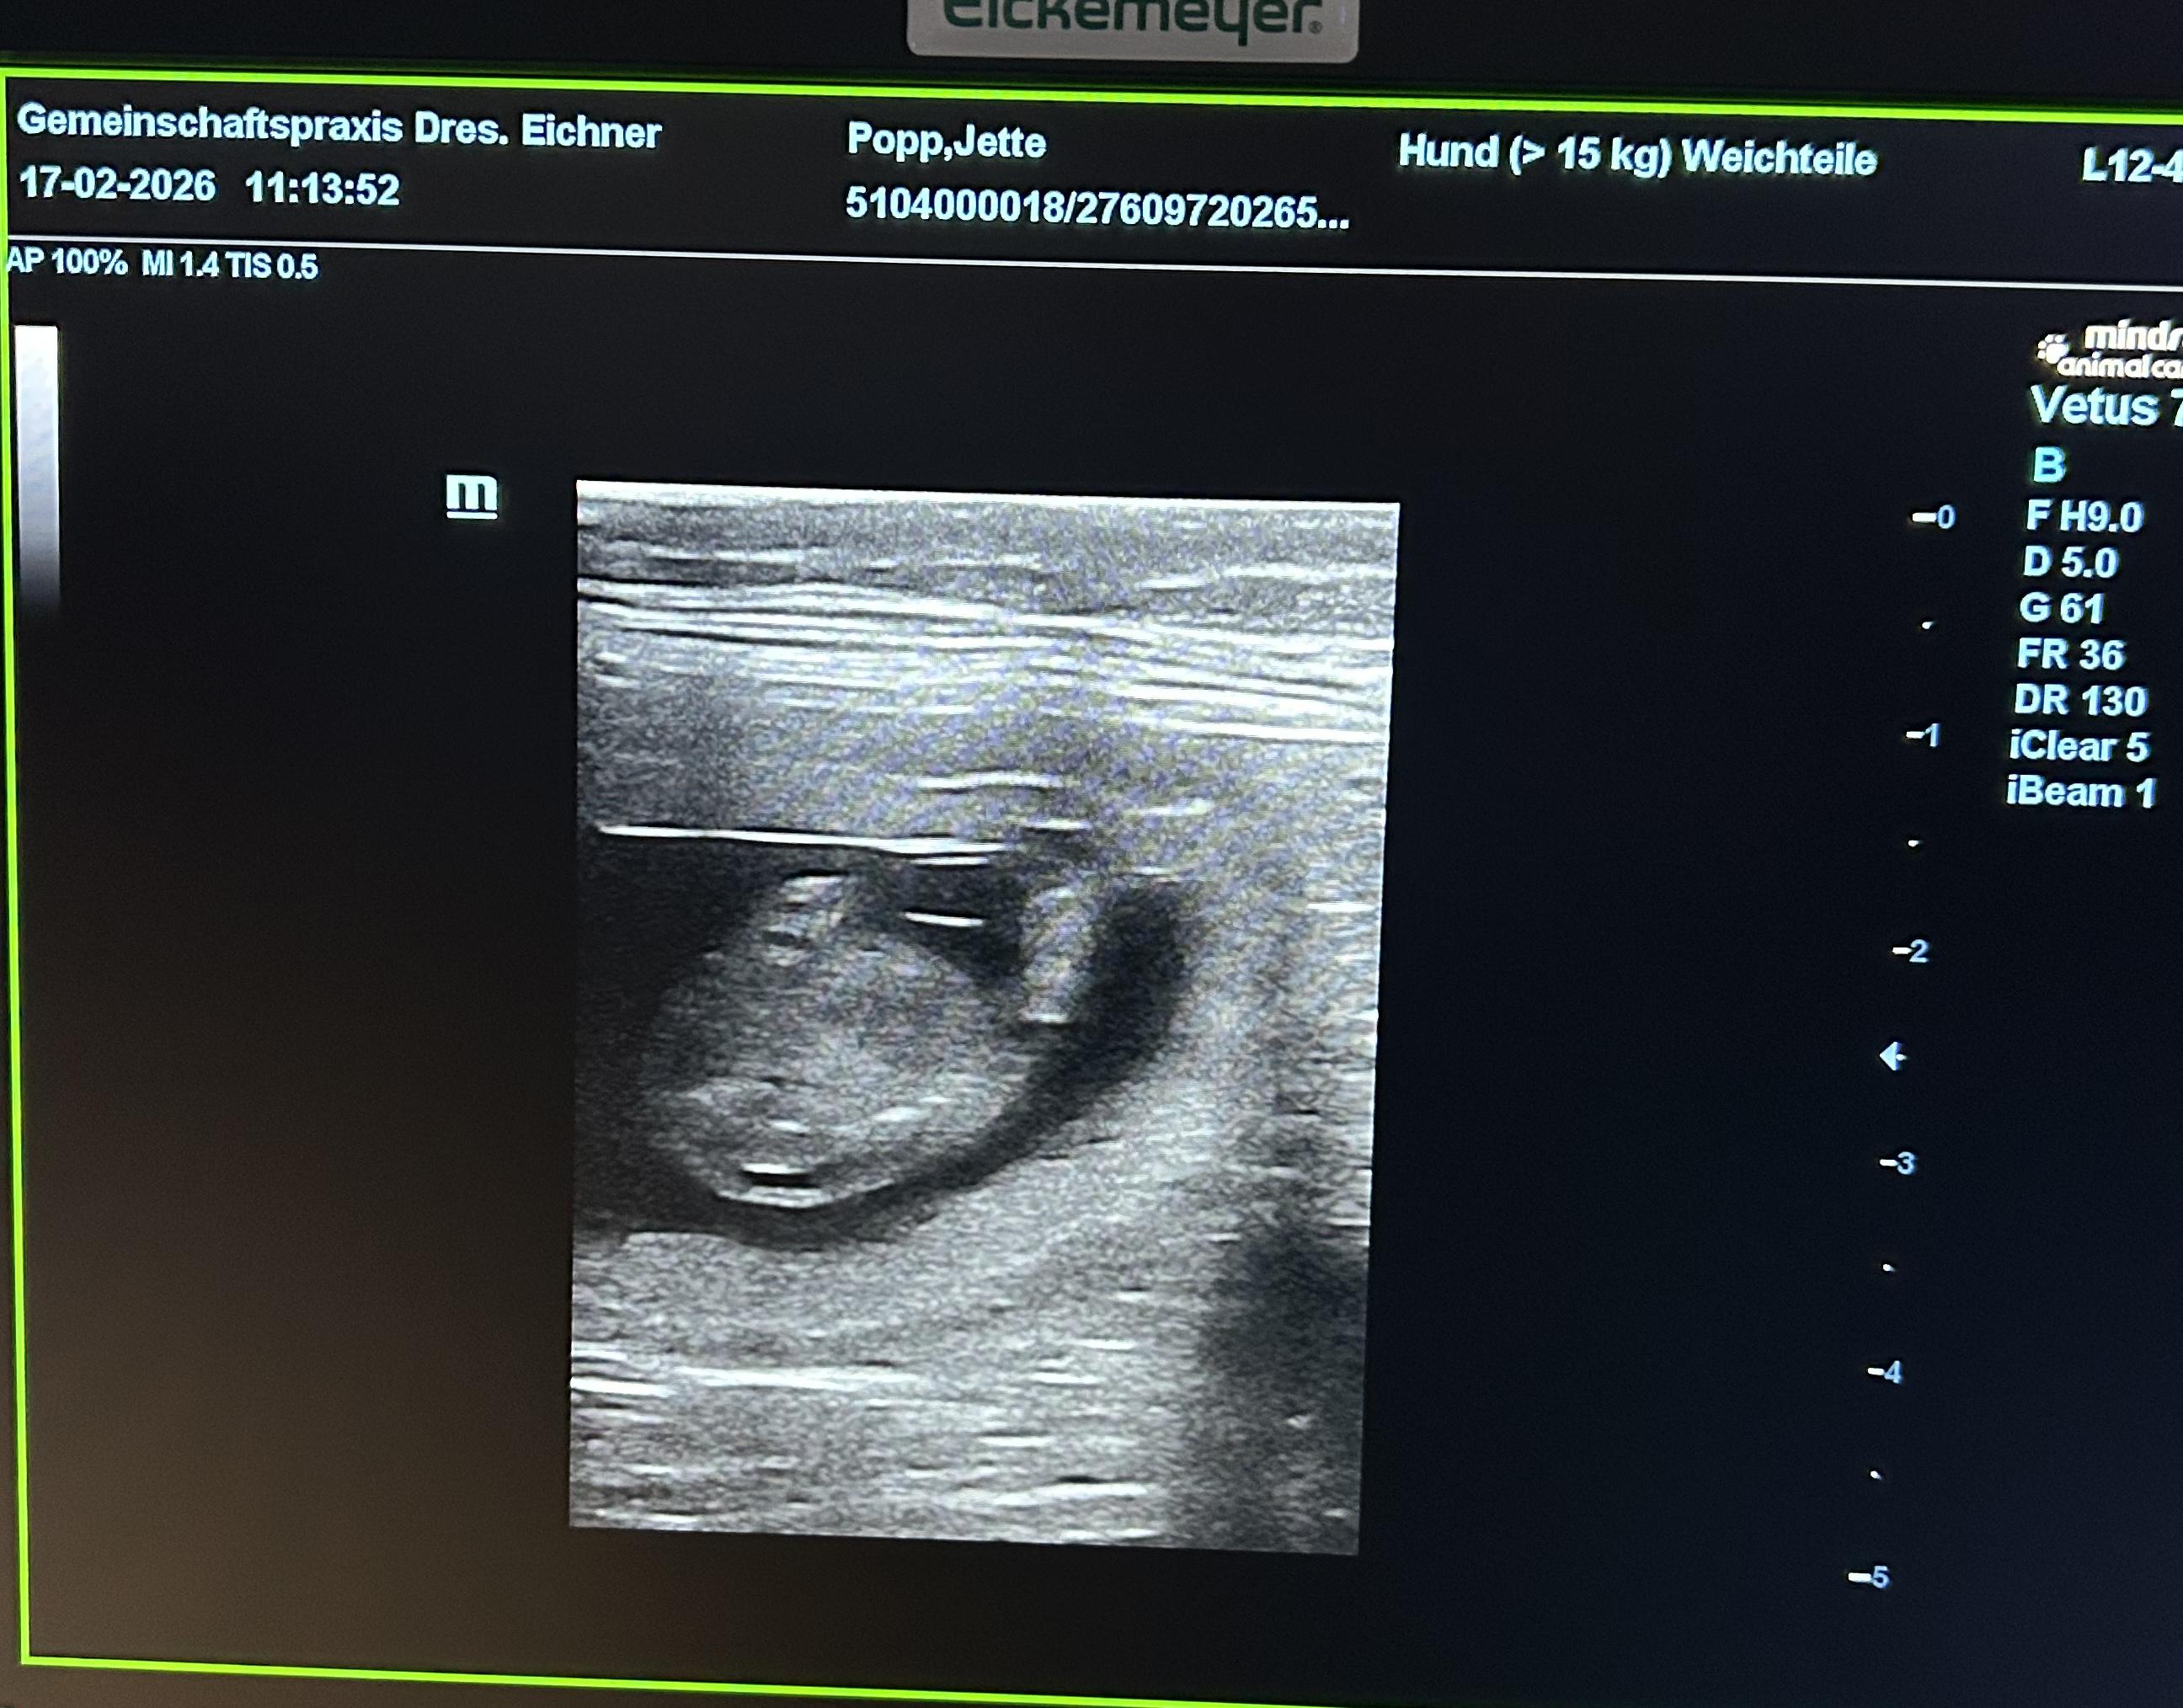

Jettes Welpen 2026

| Ultraschall | Roentgen | Geburt | 1. Woche | 2. Woche | 3. Woche | 4. Woche | 5. Woche | 6. Woche | 7. Woche | 8. Woche | 9. Woche | 10. Woche | 11. Woche | 12. Woche | 14. Woche |